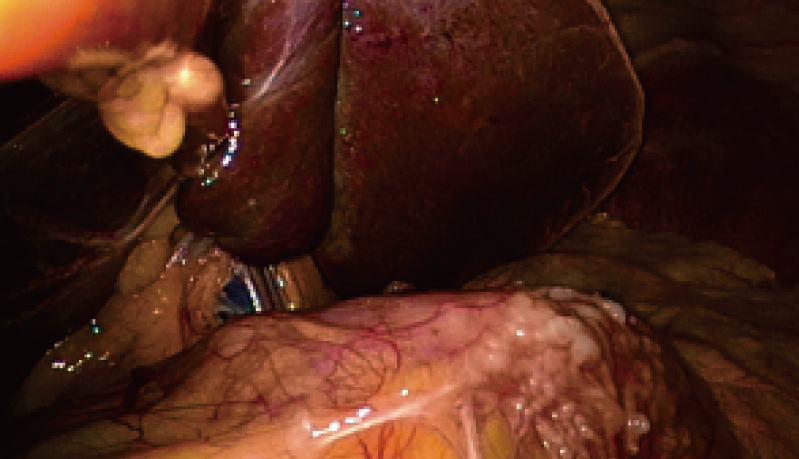

2倍光学放大

2倍电子放大